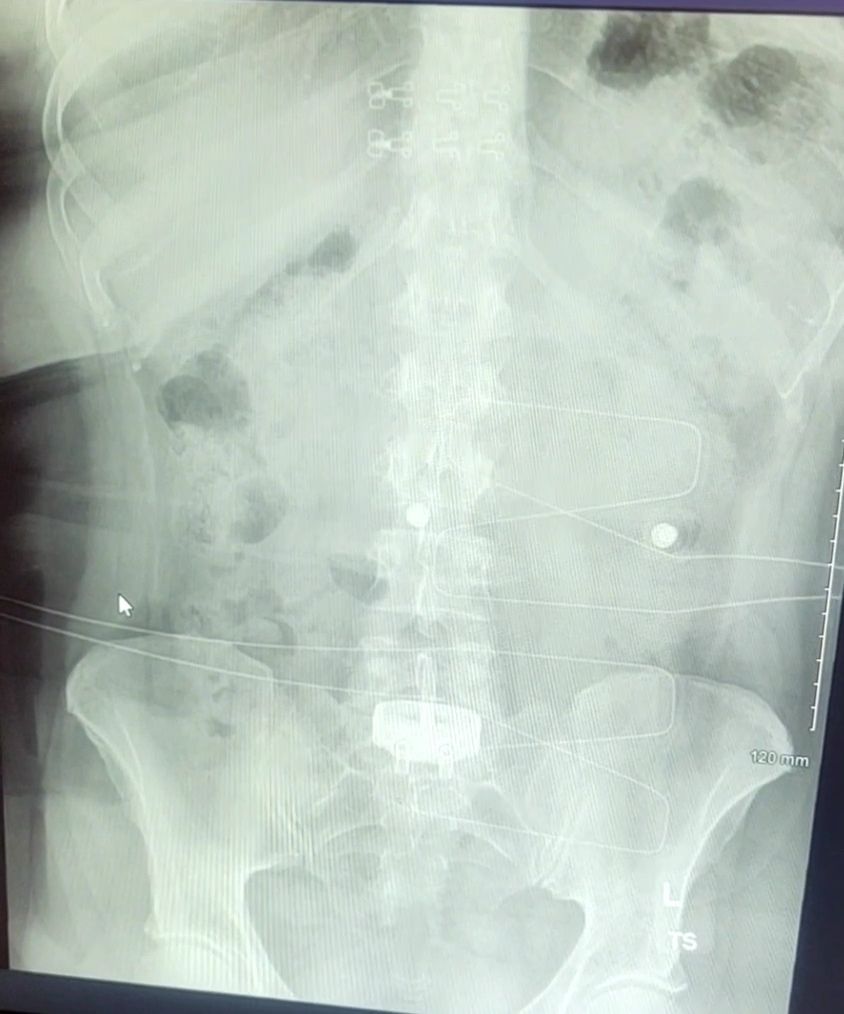

Signs of Progress: During my week three check-up, I was elated to witness a 15-degree improvement in spinal alignment through the X-rays. It was a tangible confirmation of the surgery's effectiveness. The doctor cleared me to shower, move without the brace for midnight bathroom trips, sleep on my side, and even drive short distances. Each newfound freedom brought a sense of relief and normalcy to my life.